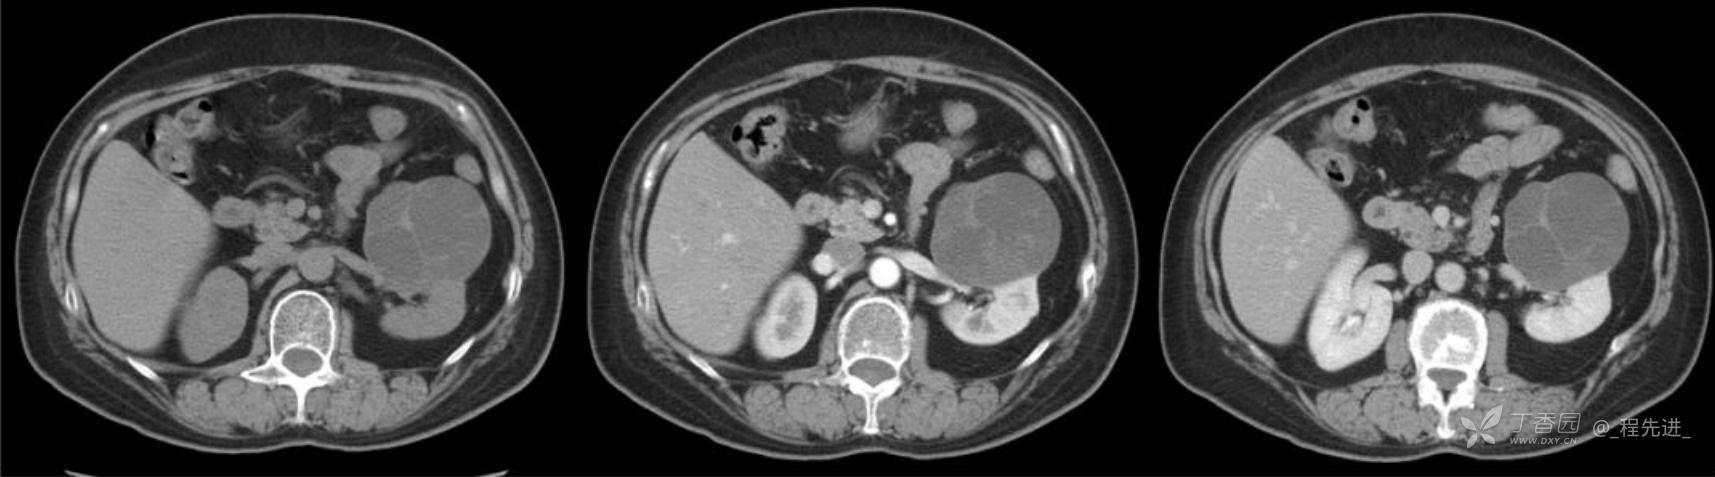

左肾罕见肿瘤病例一例

患者性别:女

患者年龄:53岁

简要病史:反复头昏、头痛5年,再发加重3月

辅助检查:无特殊,输血前检查、生化检查均正常

混合性上皮和间质肿瘤 (1)